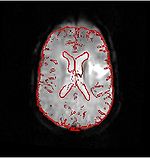

Brain.png

DTI Fiber Clustering and Fiber-Based Analysis

The goal of this project is to provide structural description of the white matter architecture as a partition into coherent fiber bundles and clusters, and to use these bundles for quantitative measurement. More...